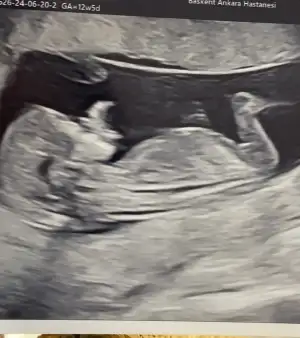

selam kızlar, kontrolümüz vardı bugün 12+5 deyiz. burun kemiği, ense ölçümleri gayet iyi. ikili yapmadık nipt testi yaptıracağımız için. kan verdik 10 güne çıkacak. cinsiyet tahmininiz varsa alırım 🥰

Eklentiler

• IMG_1803.webp

IMG_1803.webp

33,7 KB · Görüntüleme: 39